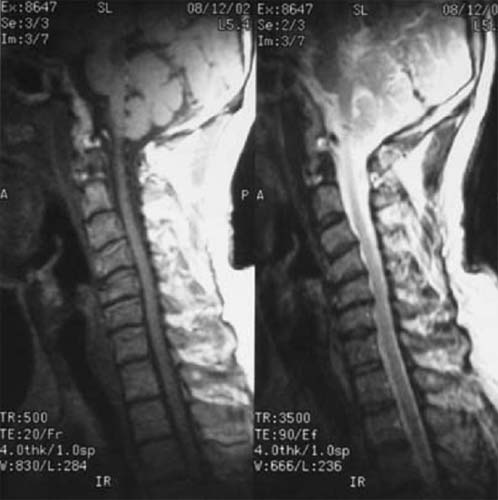

颈椎5骨折,椎体及间盘压迫硬膜囊,患者高位截瘫

前路减压,椎间植骨,钢板内固定,同期进行后路减压手术。 截瘫部分恢复,生活自理。